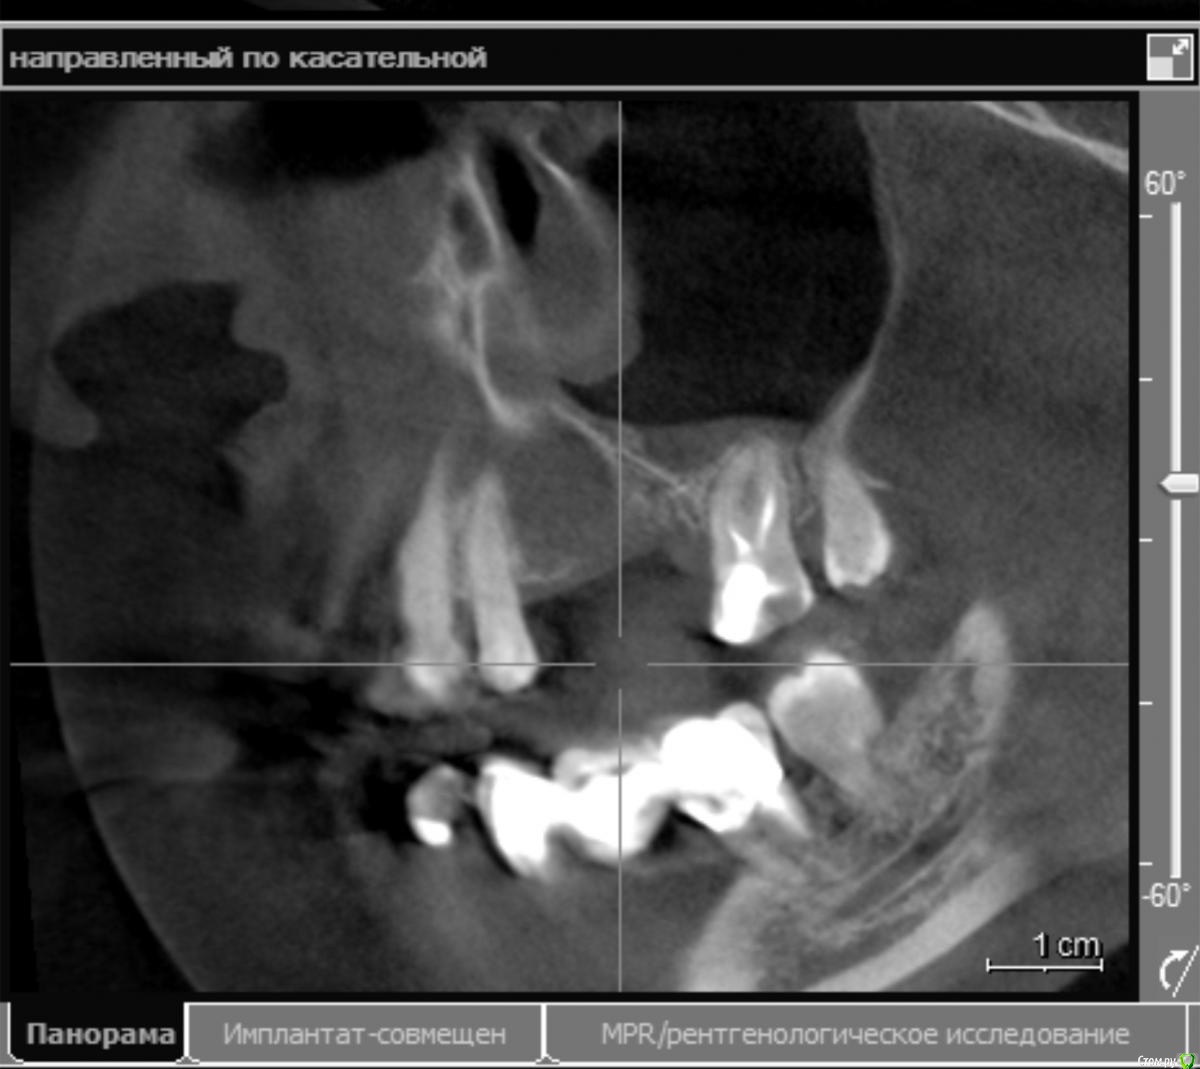

стихия Опубликовано 17 апреля, 2018 Поделиться Опубликовано 17 апреля, 2018 Здравствуйте! 8 месяцев назад были удалены верхняя левая 5-ка и 6-ка из-за кисты. Посмотрите, пожалуйста, мои снимки: возможна ли сейчас имплантация? Хватает ли там костной ткани? Проблема в том, что у меня хронический гайморит, который воспаляется каждый год, не будет ли это причиной плохой приживаемости имплантов? Можно ли при хроническом гайморите делать остеопластику? Буду очень благодарна за ответы. 2 хирурга, у которых была на очной консультации, отказались делать имплантацию в моем случае(( Ссылка на комментарий

колесников Опубликовано 17 апреля, 2018 Поделиться Опубликовано 17 апреля, 2018 (изменено) Дефект гребня в области 27 го зуба будет причиной периимплантного кармана у импланта 26. Я вижу тут 2 варианта: или Имплант Штрауман ТЛ в области 26го с синуслифтингом,+25,либо удаление 27го и мост на имплантах 25-27 Изменено 17 апреля, 2018 пользователем колесников Ссылка на комментарий

Irouil Опубликовано 17 апреля, 2018 Поделиться Опубликовано 17 апреля, 2018 Со стороны пазухи нерешаемых проблем не вижу Ссылка на комментарий